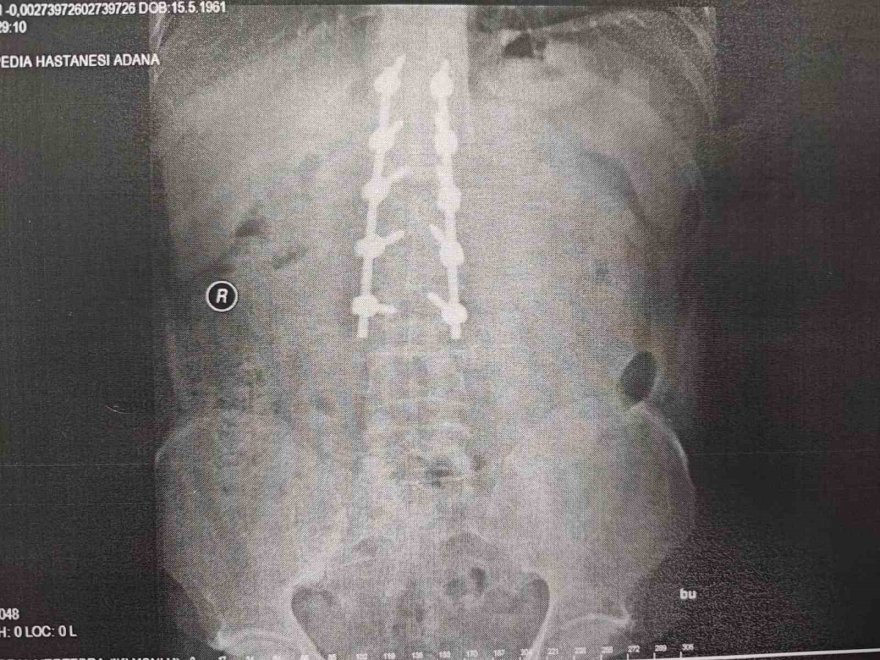

Aras, teknik hata yüzünden ölümden döndüğünü 10 platin ile yaşamak zorunda kaldığını belirterek, "Ortalama 3 ay boyunca tedavi sürecim devam etti. Omurga kemiğim kırıldı ve şuan hala 6 buçuk santim boyunda 10 tane çelik platin var. Dik durabilmem için çelik vidalar var. Ancak onların sayesinde ayakta durabiliyorum. 2019 yılında meydana geldi kaza ve bana araba artı para teklif ettiler. Bende, aynı arabanın birebir aynısı ya da bir üst modeliyle değiştirilmesini istedim. İlk önce bir alt modelini vermeyi teklif ettiler. Üstüne de para verelim dediler. Ben bunları kabul etmedim, zararımın giderilmesini istiyorum. Bayiyi hurda parça takmaktan dolayı şikayet ettim. Arabayı imal eden Mercedes'i de dava ettim" diye konuştu.